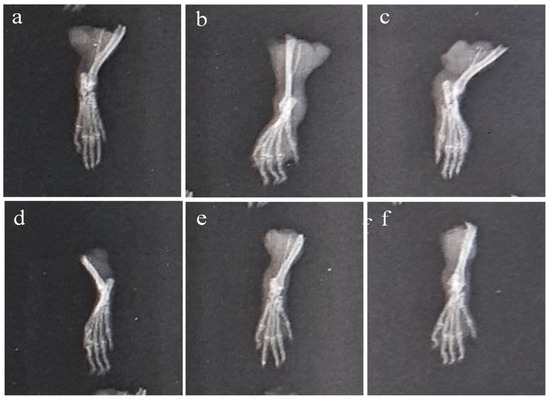

2.6.7. Histopathology of Left Hind Paw

At the end of the CFA model on the 28th day, a histopathological analysis of the paws revealed that animals treated with AeOB (750 mg/kg) (Group-VI) and indomethacin (Group-III) had considerably fewer abnormalities compared with the arthritic control (Group-II), as shown in Table 5. Figure 14 shows microscopic images of the paws of different groups.

Figure 14.

Microscopic evaluation at ×10 of CFA-induced rat paws: (a) Group-I (normal), (b) Group-II (arthritic control), (c) Group-III (standard), (d) Group-IV (AeOB, 250 mg/kg), (e) Group-V (AeOB, 500 mg/kg), and (f) Group-VI (AeOB, 750 mg/kg) on day 28 of treatment.